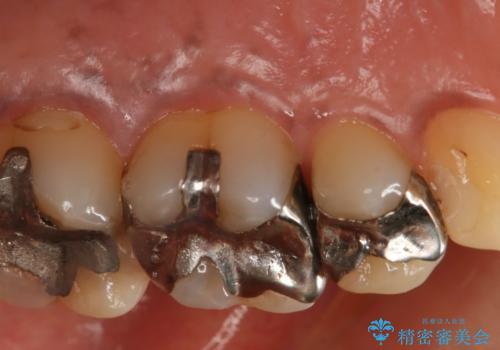

- 左上5番根尖部歯肉に膿ができ、治療を希望された患者様です。

神経が失活し根尖病変も見られるので、精密根管治療とクラウンでの治療を計画しました。

セラミックでの治療を希望されたので、フルジルコニアクラウンでの治療を選択しました。